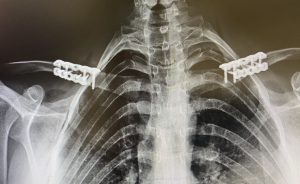

How it appears postoperatively (X-ray / CT)

- Plate fixed along the superior or anteroinferior clavicle

- Shortened clavicle length compared to preoperative imaging

- Symmetric narrowing

- Multiple bicortical screws securing the osteotomy site

- Maintained:

- AC joint alignment

- SC joint alignment

- Glenohumeral joint position